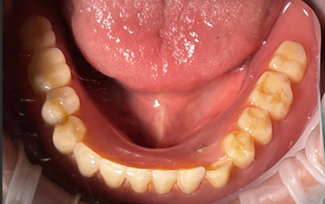

2018년 풀아치 환자분 (당시 40대 남자)

현재도 잘 사용중이세요

잇몸 반응도 지르코니아라 깨끗하구요

곱창집에서 곱창도 드시더라구요..

(곱창집 갔다가 우연히 마주침)

연구에서도 13년 성공률이 93프로에 달해요..

실제 환자분들의 깨끗한 통지르코니아 잇몸 반응